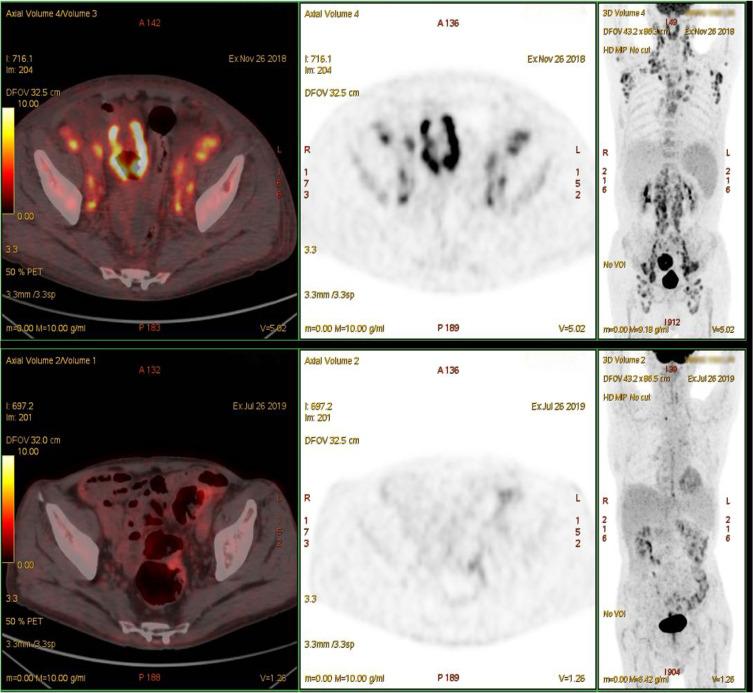

Epstein-Barr virus (EBV)-positive diffuse large B-cell lymphoma (DLBCL) complicated with angioimmunoblastic T-cell lymphoma (AITL) is extremely rare and typically shows an aggressive clinical course and unsatisfactory prognosis. Here, we describe the case of a 77-year-old man who was referred to the hospital because of repeated fever, night sweats, and weight loss. He was finally diagnosed with a discordant lymphoma consisting of AITL and DLBCL, with significantly different maximum standardized uptake values on positron emission tomography/computed tomography. Based on his complex illness and poor performance status, the patient received six cycles of lenalidomide combined with R-miniCHOP regimen and achieved complete remission with tolerable and controlled toxicity. He subsequently received lenalidomide maintenance therapy and achieved sustained remission. We consider the possible causes of this discordance involved AITL and EBV-positive DLBCL, and the possible mechanism of lenalidomide action in both T-cell and B-cell non-Hodgkin lymphomas. Lenalidomide-combination therapy may be a preferable choice in patients with an EBV-associated discordant lymphoma.

爱泼斯坦-巴尔病毒(EBV)阳性弥漫性大B细胞淋巴瘤(DLBCL)合并血管免疫母细胞性T细胞淋巴瘤(AITL)极为罕见,通常表现出侵袭性临床病程且预后不佳。在此,我们描述了一名77岁男性患者的病例,该患者因反复发热、盗汗和体重减轻而入院。他最终被诊断为一种由AITL和DLBCL组成的不一致性淋巴瘤,在正电子发射断层扫描/计算机断层扫描上具有显著不同的最大标准化摄取值。基于其复杂病情和较差的体能状态,该患者接受了六个周期的来那度胺联合R-miniCHOP方案治疗,并实现了完全缓解,且毒性可耐受和可控。随后他接受了来那度胺维持治疗并实现了持续缓解。我们考虑了这种不一致性的可能原因,涉及AITL和EBV阳性DLBCL,以及来那度胺在T细胞和B细胞非霍奇金淋巴瘤中的可能作用机制。来那度胺联合治疗可能是EBV相关不一致性淋巴瘤患者的一个较好选择。